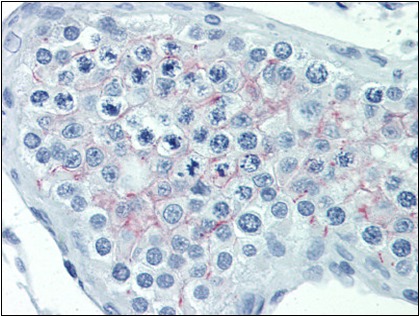

Supportive validation

- Submitted by

- Acris Antibodies GmbH (provider)

- Main image

- Experimental details

- AP23076PU-N EDG7 antibody staining of Formalin-Fixed, Paraffin-Embedded Human Testis.